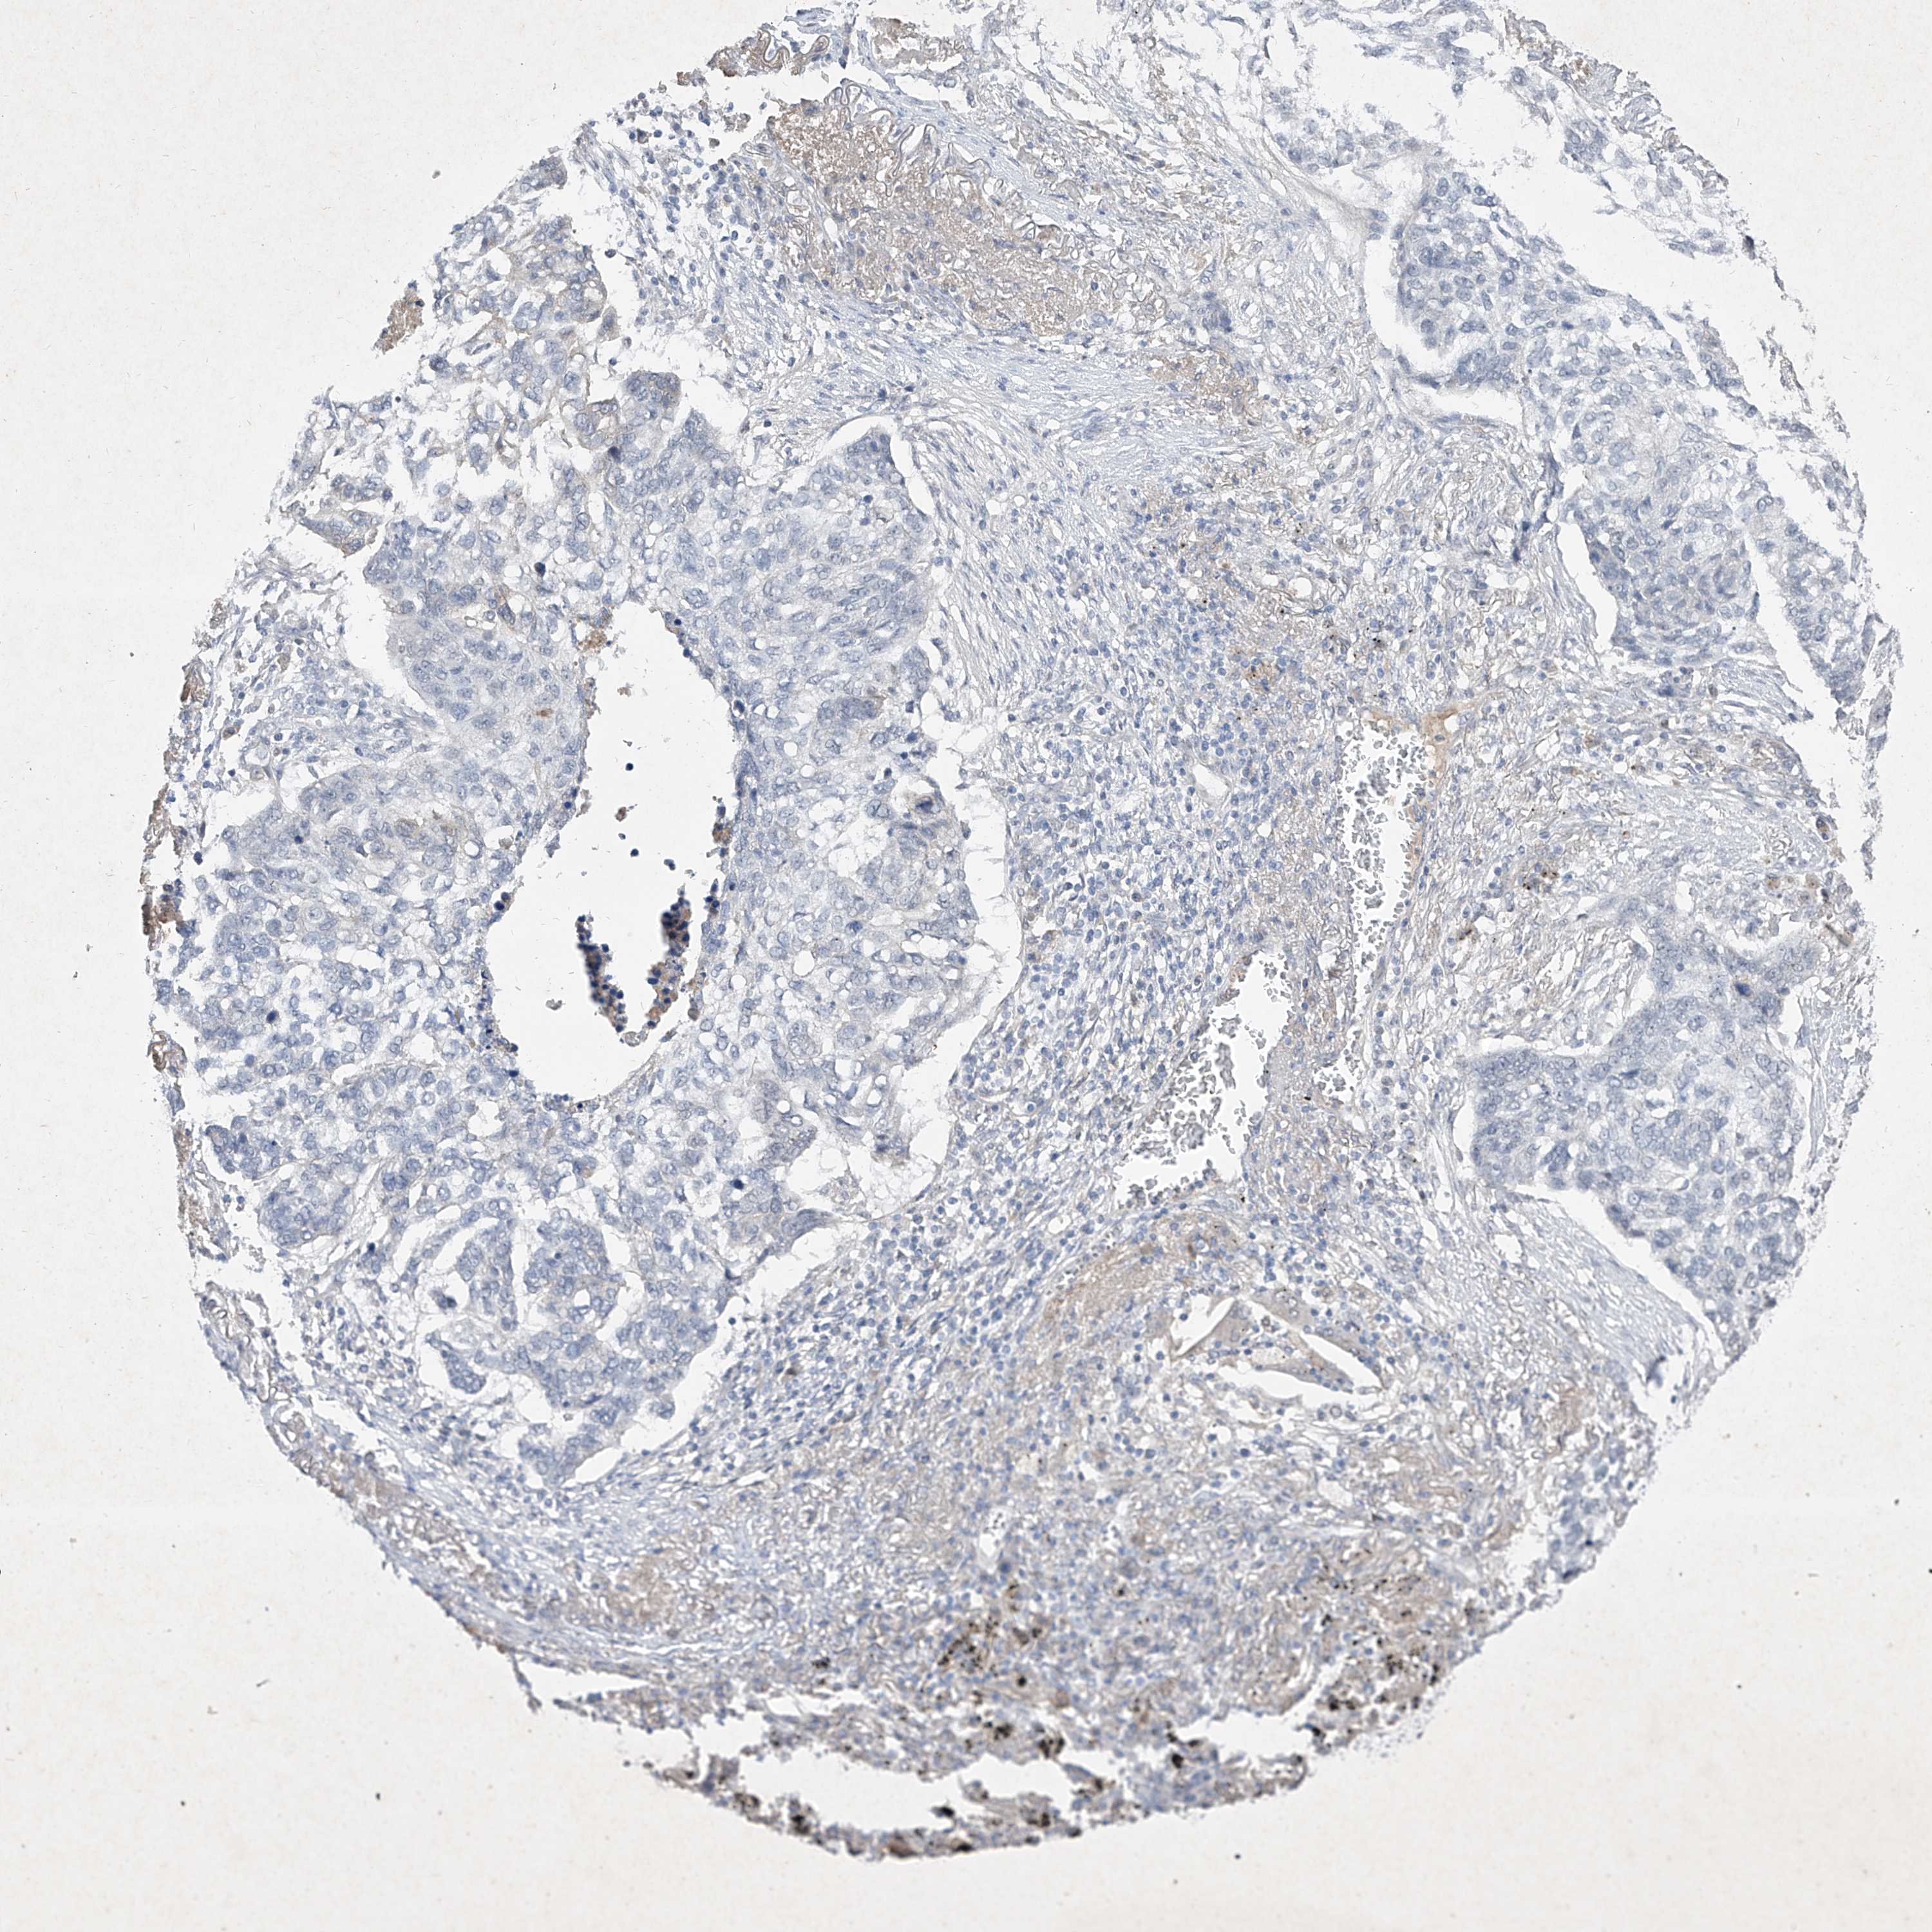

CANCER LUNG CANCER Show tissue menu

Lung cancer

Human cancer

Lung adenocarcinoma

LUNG SQUAMOUS CELL CARCINOMA (TCGA) - Interactive survival scatter ploti

C4A is not prognostic in Lung Squamous Cell Carcinoma (TCGA)